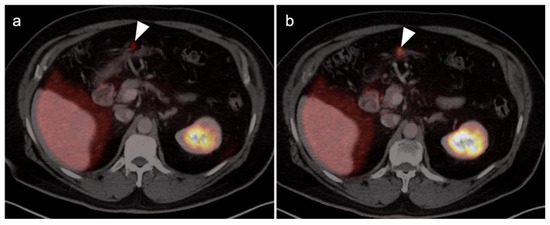

- Fuser, D.; Hedberg, M.L.; Dehner, L.P.; Dehdashti, F.; Siegel, B.A. Extensive Metastatic Sarcomatoid Renal Cell Carcinoma Evaluated by 18F-FDG PET/CT: A Case Report and Review of Literature. J. Kidney Cancer VHL 2018, 5, 1–6. [Google Scholar] [CrossRef] [PubMed]